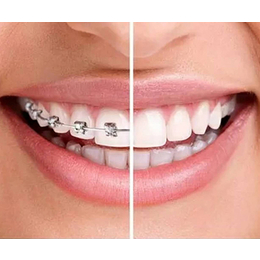

畸形牙!23岁的我终于拥有整齐的牙齿了!

畸形牙!23岁的我终于拥有整齐的牙齿了!